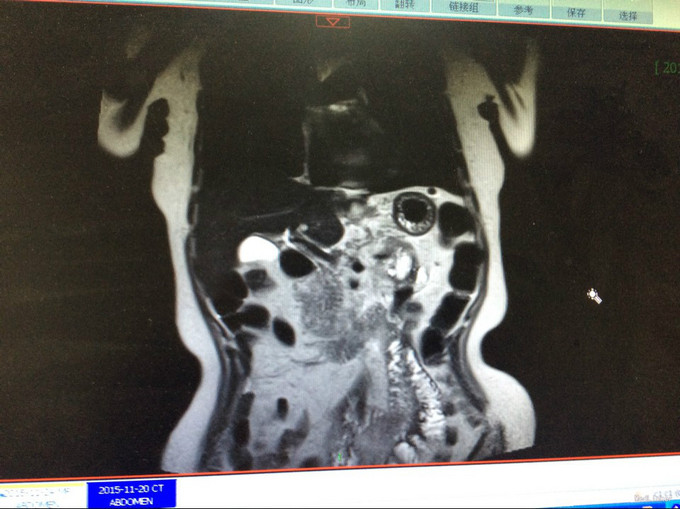

查体:生命体征平稳。神智清,查体合作,面容正常,淋巴结未触及肿大。双肺听诊呈清音,为闻及干湿罗音及哮鸣音;心率78次/分,律齐,无异常心音及心脏杂音;腹平软,肝脾肋下未及,未触及肿块,无压痛及反跳痛,肠鸣音正常。双下肢无水肿,生理反射存在,病理反射未引出。专科查体:无明显异常。辅助检查:湖北省中医院CT示:胰腺占位。CT检查示:1.结合原CT、MR检查,胰腺体尾部及周围异常改变,考虑胰腺炎伴坏死囊性变可能性大,与2015-11-20CT相比较,囊性病变略缩小;腹膜后淋巴结增多增大,大致同前;2. 所及肝脏多发囊肿;肝右叶后段其中一个病变边缘可疑强化,大小与前次相仿;3. 左侧肾上腺饱满。 MRI检查示: 胰腺体尾部及周围异常改变,考虑胰腺炎伴坏死囊性变可能性大,合并肿瘤性病变待排,病变累及腹膜伴腹膜后淋巴结增多增大,腹腔少许积液,请结合检查结果考虑;2. 所及肝脏多发囊肿;肝右叶后段其中一个病变边缘可疑强化,需鉴别于血管瘤与转移性病变,建议随访复查;3. 左侧肾上腺饱满;4. 所及右侧胸廓外小结节(层面16-7),直径约4mm,不除外右乳的病变:5. 所及腰椎骨性纵裂畸形。病理检查:(胰体尾部肿块穿刺组织)高分化腺癌,考虑为IPMN相关性浸润性癌。